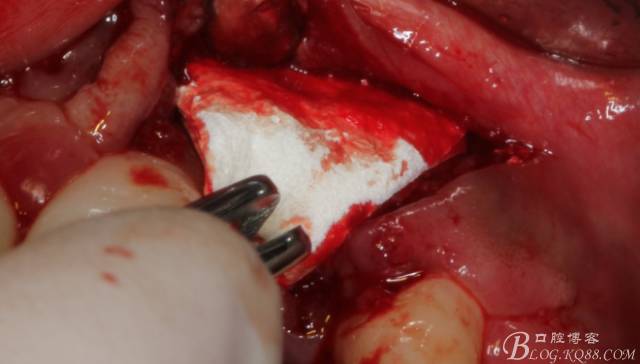

先行粘骨膜減張,取自體血液。

根方用取骨鉆取自體骨。

旋入一長(zhǎng)兩短3顆鈦釘。

將自體骨與BIO-OOS骨粉混合植到術(shù)區(qū),蓋生物膜。